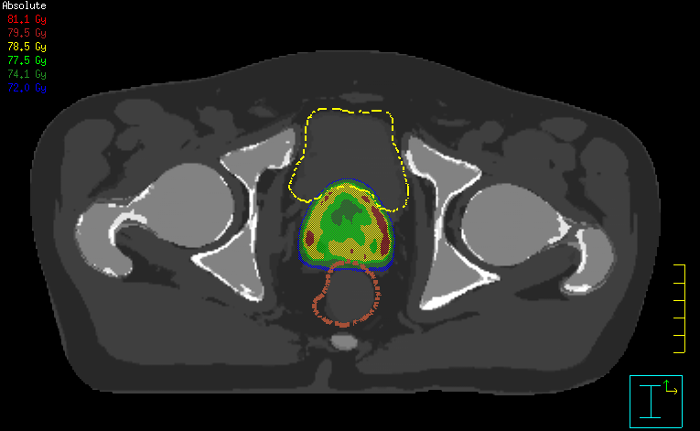

フィリップスの革新的なMRCAT (MR for Caluculating ATenuation)アプリケーションは、MRIをプライマリイメージングモダリティとして放射線治療計画に使用することができます。

MRCATで高速なMR撮像を1回*行うだけで、ターゲットとOARを描出するための高コントラストな画像とともに、線量計算用にCTと同等の電子密度情報を得ることができます。

*領域によってはさまざまなコントラストを組み合わせた撮像をします。

良好な軟部組織のコントラストのMRI画像を放射線治療計画に活用できるだけでなく、煩雑でエラーの発生しやすいCT-MRの重ね合わせ(レジストレーション)をプロセスから排除して、不確実性と複雑さを軽減できます。関連製品のクリニカルアプリケーションのセクションもご覧ください。